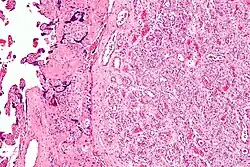

| Micrograph of a chorangioma. H&E stain. | |

- Chorangioma